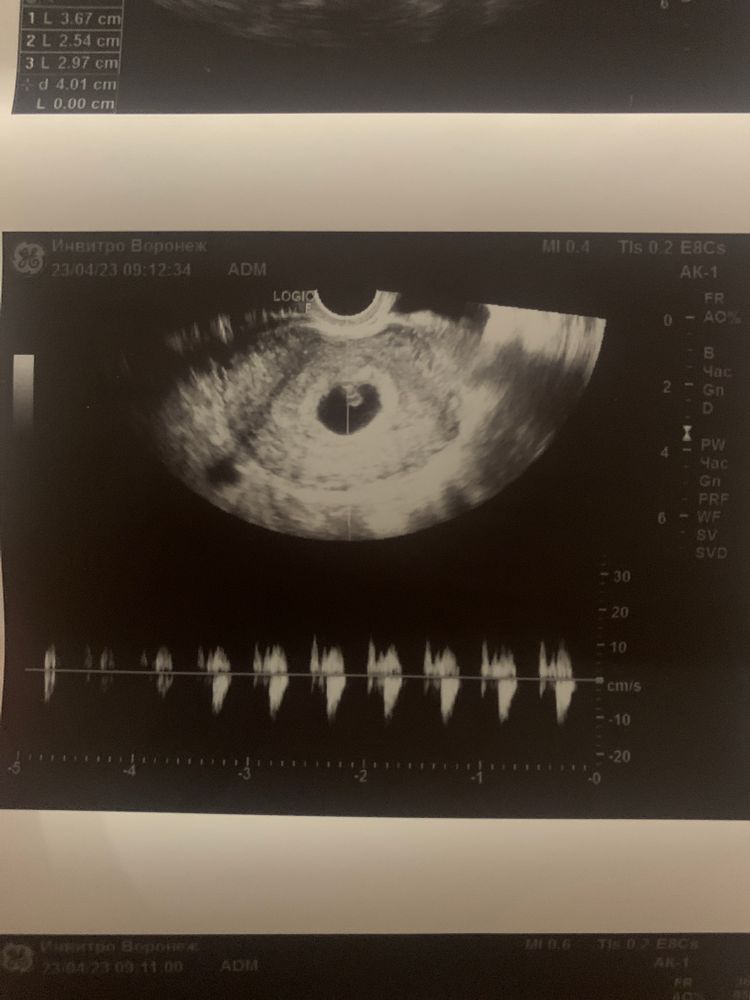

подскажите как быть ?! Стараюсь не думать и сохранять спокойствие , ходила на узи сказали 6.1 неделя , но отсутвует желтого мешочка( дословно не помню ) прописали прогестерон по 10 мг два раза в день - пью ! Сдаю кровь регулярно смотрю динамику хгч в 6.4 недели показатель - 64тыс , в 7 недель - 102 тыс , завтра 7,6 недель почти 8 пойду еще раз сдам на прием только 15 мая , сильный токсикоз ) чем чревато отсутствие желтого (мешочка) ?? Мне сказали что могут быть серьезнейщие патологии развития плода

Так на фото желточный мешочек есть,вы наверное путаете с желтым телом,а это вообще разные вещи

Непонятно о чём речь - о желточном мешочке или жёлтом теле? Скиньте текстовый протокол УЗИ! Там где написано про плодное яйцо и яичники..